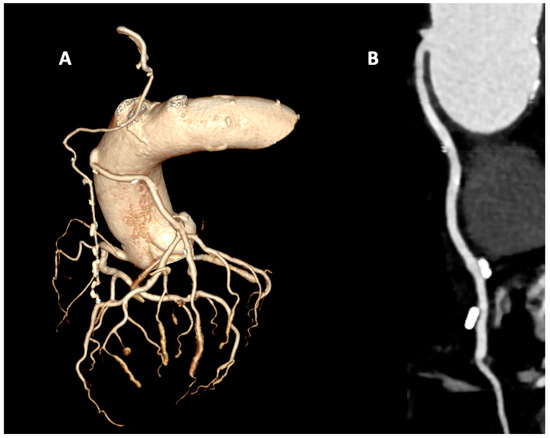

Multimodality Cardiovascular Imaging in Patients After Coronary Artery Bypass Grafting: Diagnosis and Risk Stratification

by Lucia La Mura, Annalisa Pasquini, Adriana D′Antonio, Eirini Beneki, Irfan Ullah, Ashot Avagimyan, Mahmoud Abdelnabi, Ramzi Ibrahim, Vikash Jaiswal and Francesco Perone

Coronary artery bypass grafting (CABG) remains a cornerstone of treatment for patients with advanced or complex coronary artery disease, yet long-term success is influenced by graft patency, progression of native disease, and ventricular remodeling. Optimizing the follow-up of these patients requires a structured [...] Read more.

Coronary artery bypass grafting (CABG) remains a cornerstone of treatment for patients with advanced or complex coronary artery disease, yet long-term success is influenced by graft patency, progression of native disease, and ventricular remodeling. Optimizing the follow-up of these patients requires a structured approach in which multimodality cardiovascular imaging plays a central role. Echocardiography remains the first-line modality, providing readily available assessment of ventricular function, valvular competence, and wall motion, while advanced techniques, such as strain imaging and myocardial work, enhance sensitivity for subclinical dysfunction. Coronary computed tomography angiography (CCTA) offers excellent diagnostic accuracy for graft patency and native coronary anatomy, with emerging applications of CT perfusion and fractional flow reserve derived from CT (FFR-CT) expanding its ability to assess lesion-specific ischemia. Cardiovascular magnetic resonance (CMR) provides comprehensive tissue characterization, quantifying scar burden, viability, and inducible ischemia, and stress CMR protocols have demonstrated both safety and independent prognostic value in post-CABG cohorts. Nuclear imaging with single-photon emission computed tomography (SPECT) and positron emission tomography (PET) remains essential for quantifying perfusion, viability, and absolute myocardial blood flow, with hybrid PET/CT approaches offering further refinement in patients with recurrent symptoms. In patients after CABG, multimodality imaging is tailored to the patient’s characteristics, symptoms, and pre-test probability of disease progression. In asymptomatic patients, imaging focuses on surveillance, risk stratification, and the early detection of subclinical abnormalities, whereas in symptomatic individuals, it focuses on establishing the diagnosis, defining prognosis, and guiding therapeutic interventions. Therefore, the aim of our review is to propose updated and comprehensive guidance on the crucial role of multimodality cardiovascular imaging in the evaluation and management of post-CABG patients and to provide a practical, evidence-based framework for optimizing outcomes. Full article